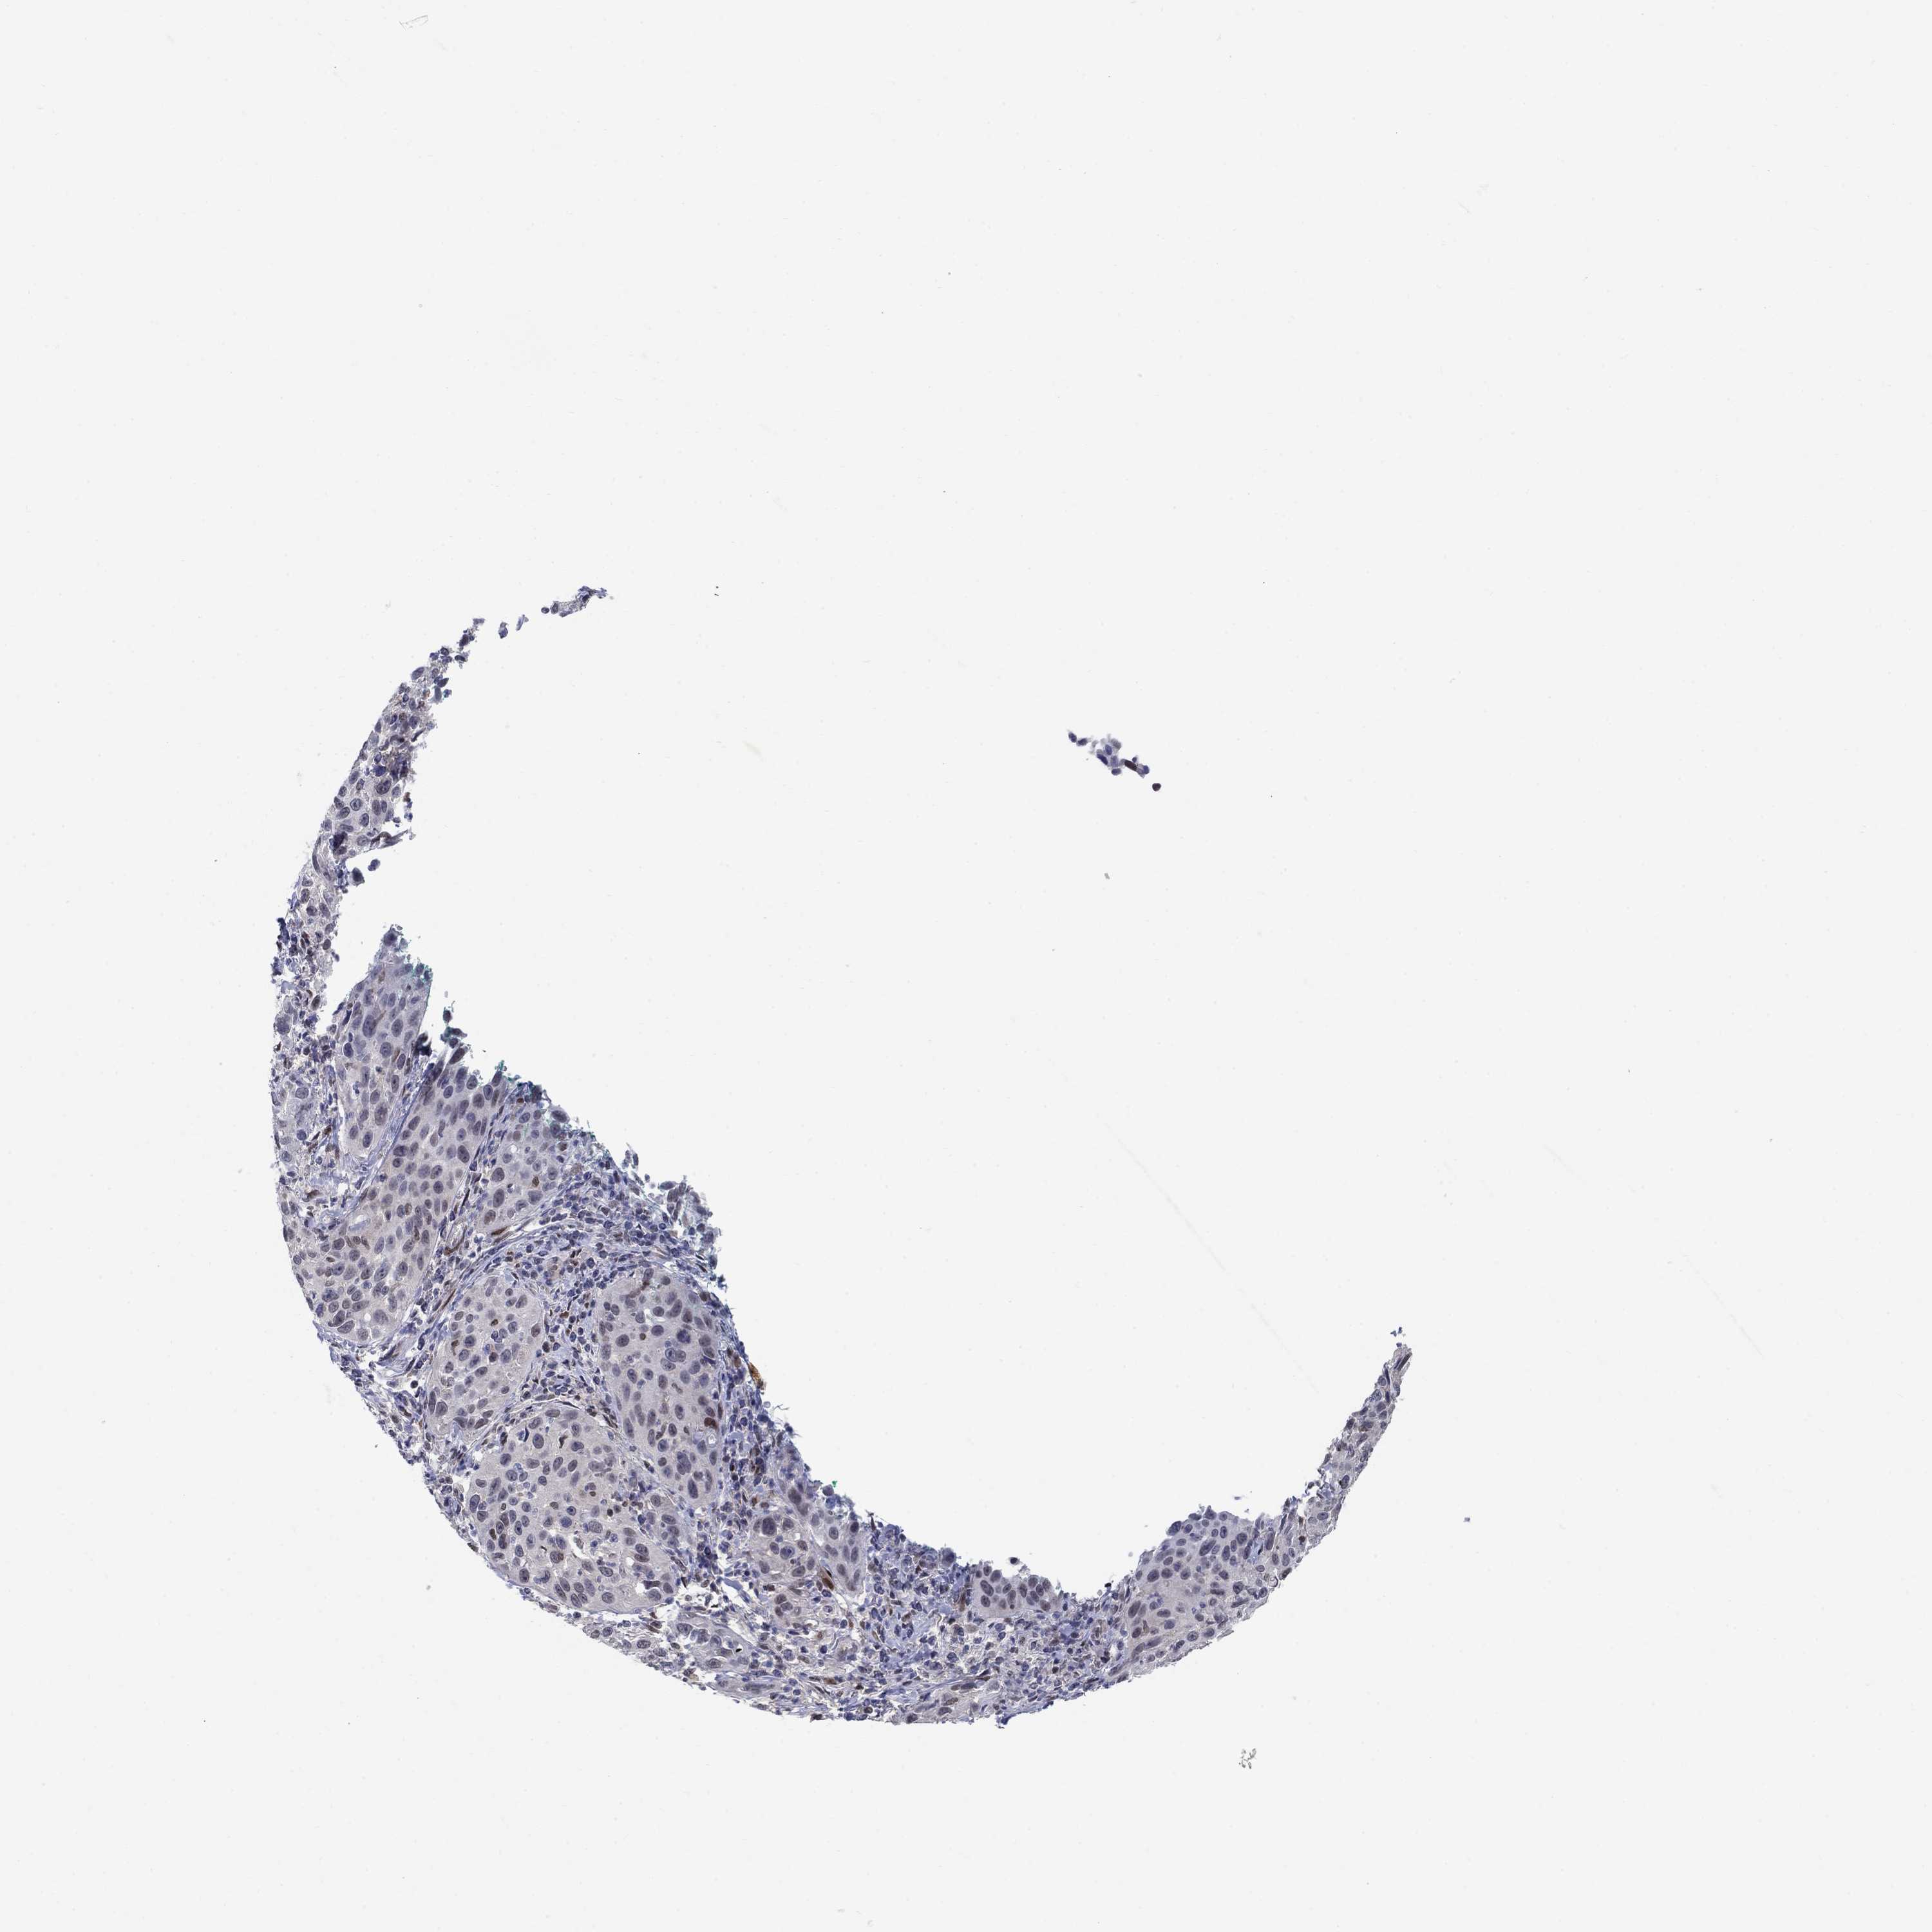

CERVICAL CANCER - Protein expressioni

A mouse-over function shows sample information and annotation data. Click on an image to view it in a full screen mode. Samples can be filtered based on level of antibody staining by selecting one or several of the following categories: high, medium, low and not detected. The assay and annotation is described here.

Note that samples used for immunohistochemistry by the Human Protein Atlas do not correspond to samples in the TCGA dataset.

Antibody stainingi

Antibody staining in the annotated cell types in the current human tissue is reported as not detected, low, medium, or high, based on conventional immunohistochemistry profiling in selected tissues. This score is based on the combination of the staining intensity and fraction of stained cells.

Each image is clickable and will lead to virtual microscopy that enables deeper exploration of all samples and also displays staining intensity scores, fraction scores and subcellular localization as well as patient and tissue information for each sample.

Antibody HPA042294

Staining

High

Medium

Low

Not detected

Intensity

Strong

Moderate

Weak

Negative

Quantity

>75%

75%-25%

<25%

None

Location

Nuclear

Cytoplasmic/membranous

Cytoplasmic/membranous,nuclear

Squamous cell carcinoma, NOS

Adenocarcinoma, NOS